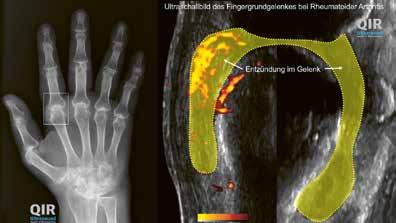

Anschliessend wird die Diagnose meistens durch ergänzende Labor, Ultraschall und Röntgenuntersuchungen nochmals überprüft. Diese Untersuchungen schliessen andere Erkrankungen aus und lassen die Schwere und den wahrscheinlichen Verlauf der rheumatoiden Arthritis besser einschätzen.

Im Blutbild weisen erhöhte Entzündungswerte, die typischen Rheumafaktoren und Autoantikörper (AntiCCPAntikörper) auf eine hohe Krankheitsaktivität (Schub) und eine möglicherweise schlechtere Prognose für den Krankheitsverlauf hin. Im Ultraschall wird nach einer verdickten Gelenkschleimhaut, vermehrter Gelenkflüssigkeit und durchblutung und insbesondere nach kleinen Schadstellen im gelenknahen Knochen gesucht. Diese Schadstellen werden Erosionen genannt. Die Erosionen und, falls vorhanden, auch ein durch die Entzündungsprozesse mitbegünstigter Knochenschwund (Osteoporose) werden in Röntgenbildern von Händen und Füssen festgehalten. Spätestens nach einem Jahr werden sie mit dem vorherigen Zustand verglichen.

Oben: Gesundes Fingergrundgelenk im Röntgen (links) und Ultraschallbild (rechts).

Unten: Fingergrundgelenk bei RA im Röntgen (links) und Ultraschallbild (rechts).